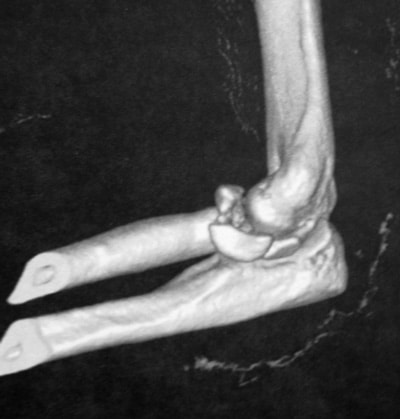

Luxation trans olécranienne

Dans ce cas, réduction au bloc est ostéosynthèse par plaque verrouillée.